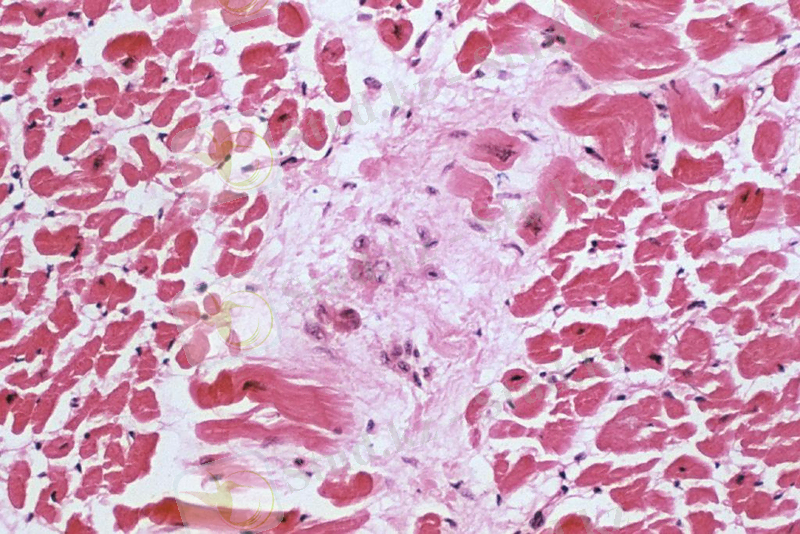

Сурет 1. Миокардтағы альтернативті қабыну

Ағымы бойынша 2 түрге бөлінеді: өткір және созылмалы. Өткір формасы кезінде паренхиматозды торшаларда дистрофиялық өзгерістер мен некроз болады. Жиі түйіршікті, вакуольді шырышты дистрофия, майлы дистрофия. Кілегей қабықтарында эпителилердің түсуі байқалады (десквамативті катар) . Экссудативті өзгерстер гиперемия түрінде, ал пролиферативті - бөгде дәнекер - ұлпалы торшалардың көбеюі түрінде көрінеді. Өткір формасының мысалдарына жатады: қауіпті аусыл кезінде өткір альтеративті миокардит, туберкулез кезінде казеозды пневмония және т. б. Созылмалы формасы кезінде әлсіз токсинді факторлардың (азықтық интоксикация және токсикоинфекция) ұзақ уақыт әсер етуі салдарынан атрофиялық өзгерістерге ие болады. Патогенезі терең метаболикалық бұзылыстармен және пролиферативтік құбылыстармен сүйемелденетін, ағзаның паренхиматозды элементтеріне патогенді факторлардың тікелей әсер етуіне байланысты. Өткір ағым кезінде макроскопиясында паренхиматозды ағзалар (бауыр, бүйрек және т. б. ) ұлғайған, борпылдақ, күңгірт, гиперемияланған немесе түзу емес көрінетін тамыр реакциялы және ала бейнелі (қою-қызыл және сұр-сары аумақты), кейде жеке қанталаулары болады. Жүрек бұлшық еттерінің беткейлік кесіндісінде жолбарыс терісінің суретіне ұқсас болады (өткір миокардит кезінд жолбарысты жүрек) . Өкпесі казеозды пневмония жағыдайында. Лимфа түйіндері - сәулелі казеозды лимфаденитті. Созылмалы ағым кезінде ағзалардың көлемі ұлғайған, тығыз, капсулалы. Кескен кезде сұр-қызыл және сұр - ақшыл аумақтары және ұзарған дәнекер ұлпалары байқалады. Өткір кезеңде гистологиясы байқалады, ең бастысы дистрофиялық (көмірсулы, түйіршікті және гидротикалық дистрофия, майлы декомпозиция, кілегей қабықтар эпителилерінің кілегейлі дистрофиясы) және некротикалық үрдістер, эпители қабаты түсіп қалады. Тамырлы реакциясы қабынған гиперемия және ісік түрінде әлсіз көрінеді, кейде диапедезді түрдегі қанталаулар байқалады. Жас дәнекер ұлпалы торшалардың пролиферациясы білінеді. Созылмалы ағым кезінде паренхиматозды торшалардағы атрофиялық үрдістер дәнекер ұлпасының паренхимасымен байланысқан. Ақыры қабынған ағзаның зақымдалу дәрежесіне, ұлпаның зақымдалу тереңділігіне және оның функциональдық маңыздылығына байланысты. Жеңіл дәрежелері ешқандай ізсіз өтеді, ұлпалары толық қалыпқа келеді. Жүйке ұлпаларындағы альтеративті қабыну кезінде және миокардтағы болжамы, әдетте қолайсыз болады. Одан басқа, қабынудың ақыры зақымдалу дәрежесіне және зақымдалған ағза түріне байланысты. Әсіресе, жүйке жүйесі мен миокардтағы альтеративті қабыну қауіпті. Ол жиі, дәнекер ұлпасының өсіумен және оның паренхимасымен байланысуымен қабыну үрдісінің толық емес түрі бойынша аяқталады. Егер өлім болмаса, өлі ұлпа дәнекер ұлпасымен бірігеді (склероз) . Қазір көптеген қабыну дамуына қатысатын биологиялық белсенді заттар зерттелген. Оларды: жасушалардан пайда болатын (жасушалық) дәнекерлер және қан плазмасында болатын (гуморалдық) - медиаторлар деп екі топқа бөледі. Жасушалық медиаторларға гистамин, серотонин, лизосомалық ферменттер, катиондық нәруыздар, лимфокиндер, простагландиндер, циклдік нуклеотидтер жатады. Қан плазмасында калликреинкининді, комплемент және қан ұю жүйесіне қатысатын заттар болады және олар әсерленеді, қабыну дамуына дәнекерлер болады. Гистамин мес жасушаларда немесе лаброциттерде гепаринмен және химазамен байланысқан әсерсіз түрде болады. Бос күйінде ол ұсақ тамырларға (капиллярлар, венулалар), олардың кемерлерінің өткізгіштігін көтеріп, кеңітетін әсер етеді. Гистамин аз мөлшерде артериолаларды кеңітеді, ал көп мөлшерде - венулаларды жиырады.